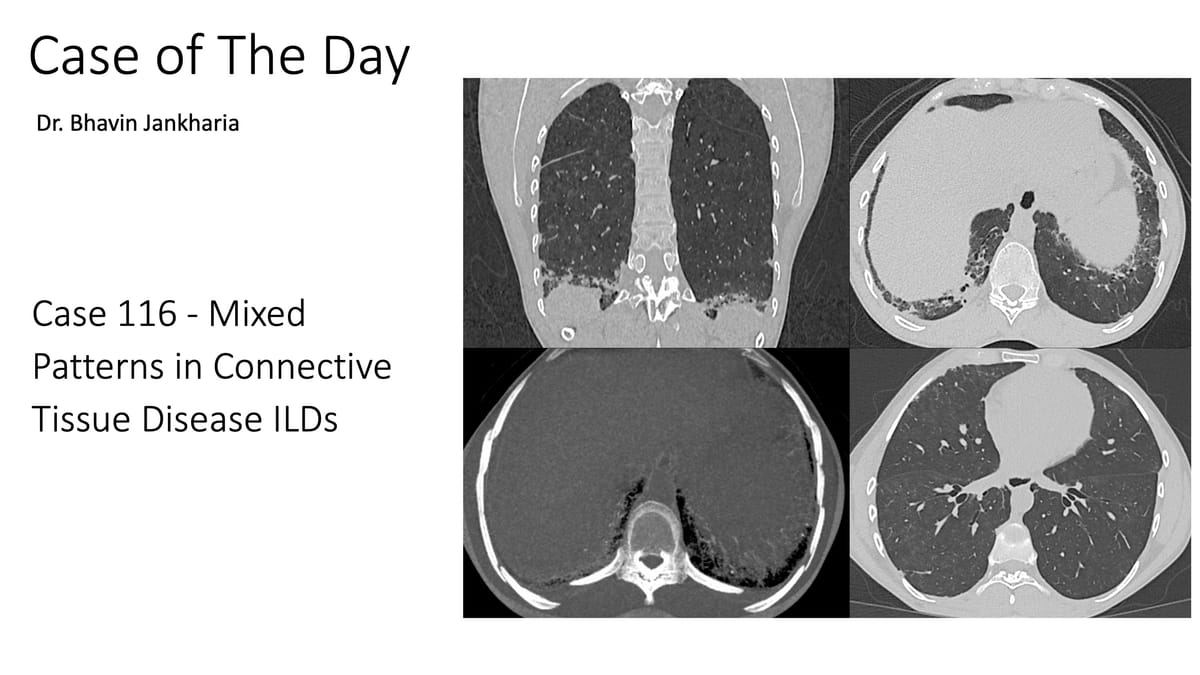

COD 117 - A Progressive Mixed Pattern Preceding the CTD Diagnosis

51-yrs old in 2012 presented with a fibrotic NSIP pattern.

The video describes the temporal evolution from 2017 to 2025 with a mixed pattern of fibrotic NSIP, fibrotic OP and DPO/CiOP and a final CTD diagnosis that was established only early this year with evidence of PPF.